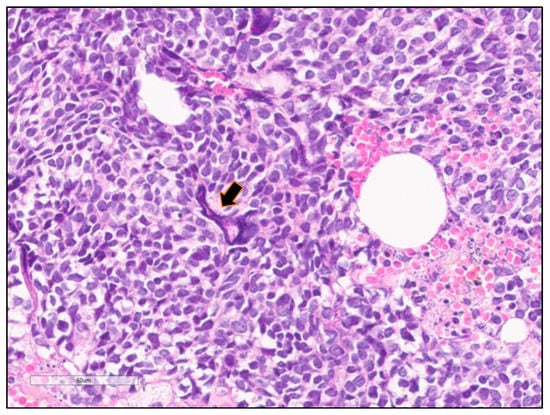

4.1. Cytological Features

4.2. Histopathological Features